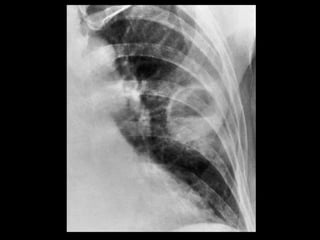

Mucormicose